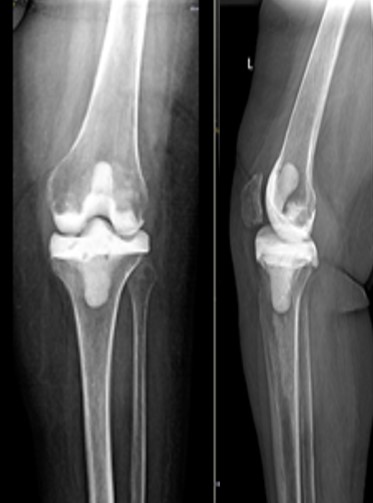

Приклад 3. Хвора К. 52 років. Діагноз: Деформівний IVст. гонартроз, стан після ТЕП лівого КС (2013р.). ІМТ хворої складає 35 балів. Асептична нестабільність компонентів ендопротеза лівого колінного суглоба, міграція великогомілкового компоненту (2017 р.) (рис. 2 а). Хворій виконано ревізійне ендопротезування: видалення компонентів ендопротезу, виявлений дефект медіального виростку великогомілкової кістки тип Т3А за класифікацією АОRI [G.A. Engh, C.H. Rorabeck, 1997]. Під час операції виконана кісткова пластика дефекту. Використаний ендопротез колінного суглоба з подовжувачами.